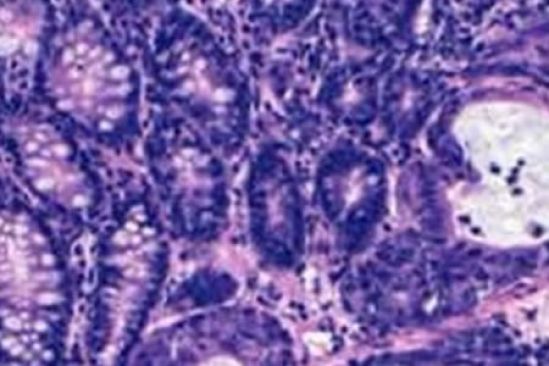

Ciudad de México. En México, el cáncer de mama se ha convertido en la primera causa de decesos en mujeres mayores de 25 años, se estima que cada dos horas muere una mujer por este padecimiento debido a que en nuestro país el 90% de las detecciones se hacen en etapas III y IV, de las cuales el 45 y 60% se encuentran en un rango de edad menor a 50 años.

Desafortunadamente cerca del 30%1 de estas mujeres en fase inicial, progresan a una enfermedad metastásica y a partir de ese instante se enfrentan a un reto de supervivencia, en el cual factores como el diagnóstico oportuno, tratamiento adecuado y atención temprana son vitales y necesarios para enfrentar la batalla que está por venir.